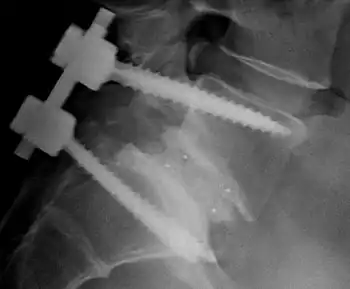

There are many types of spinal fusion techniques. Each technique varies depending on the level of the spine and the location of the compressed spinal cord/nerves.[4] After the spine is decompressed, bone graft or artificial bone substitute is packed between the vertebrae to help them heal together.[2] In general, fusions are done either on the anterior (stomach), posterior (back), or both sides of the spine.[4] Today, most fusions are supplemented with hardware (screws, plates, rods) because they have been shown to have higher union rates than non-instrumented fusions.[4] Posterior lumbar spinal fixation using the conventional pedicle screw trajectory is the most common technique used in lumbar spine fusion. However, the stability of pedicle screws can be compromised in individuals with reduced bone density, which may lead to implant failure and pseudoarthrosis. The cortical bone trajectory (CBT) screw technique has been introduced as an alternative to the traditional pedicle screw trajectory for posterior spinal fixation. CBT screws are smaller and inserted along a caudo-cranial, mediolateral pathway. By engaging the denser cortical bone, CBT screws provide greater anchorage and may be more suitable for patients with osteoporosis.[13][14] Minimally invasive techniques are also becoming more popular.[15] These techniques use advanced image guidance systems to insert rods/screws into the spine through smaller incisions, allowing for less muscle damage, blood loss, infections, pain, and length of stay in the hospital.[15] The following list gives examples of common types of fusion techniques performed at each level of the spine:

- Posterolateral fusion is a bone graft between the transverse processes in the back of the spine. These vertebrae are then fixed in place with screws or wire through the pedicles of each vertebra, attaching to a metal rod on each side of the vertebrae.